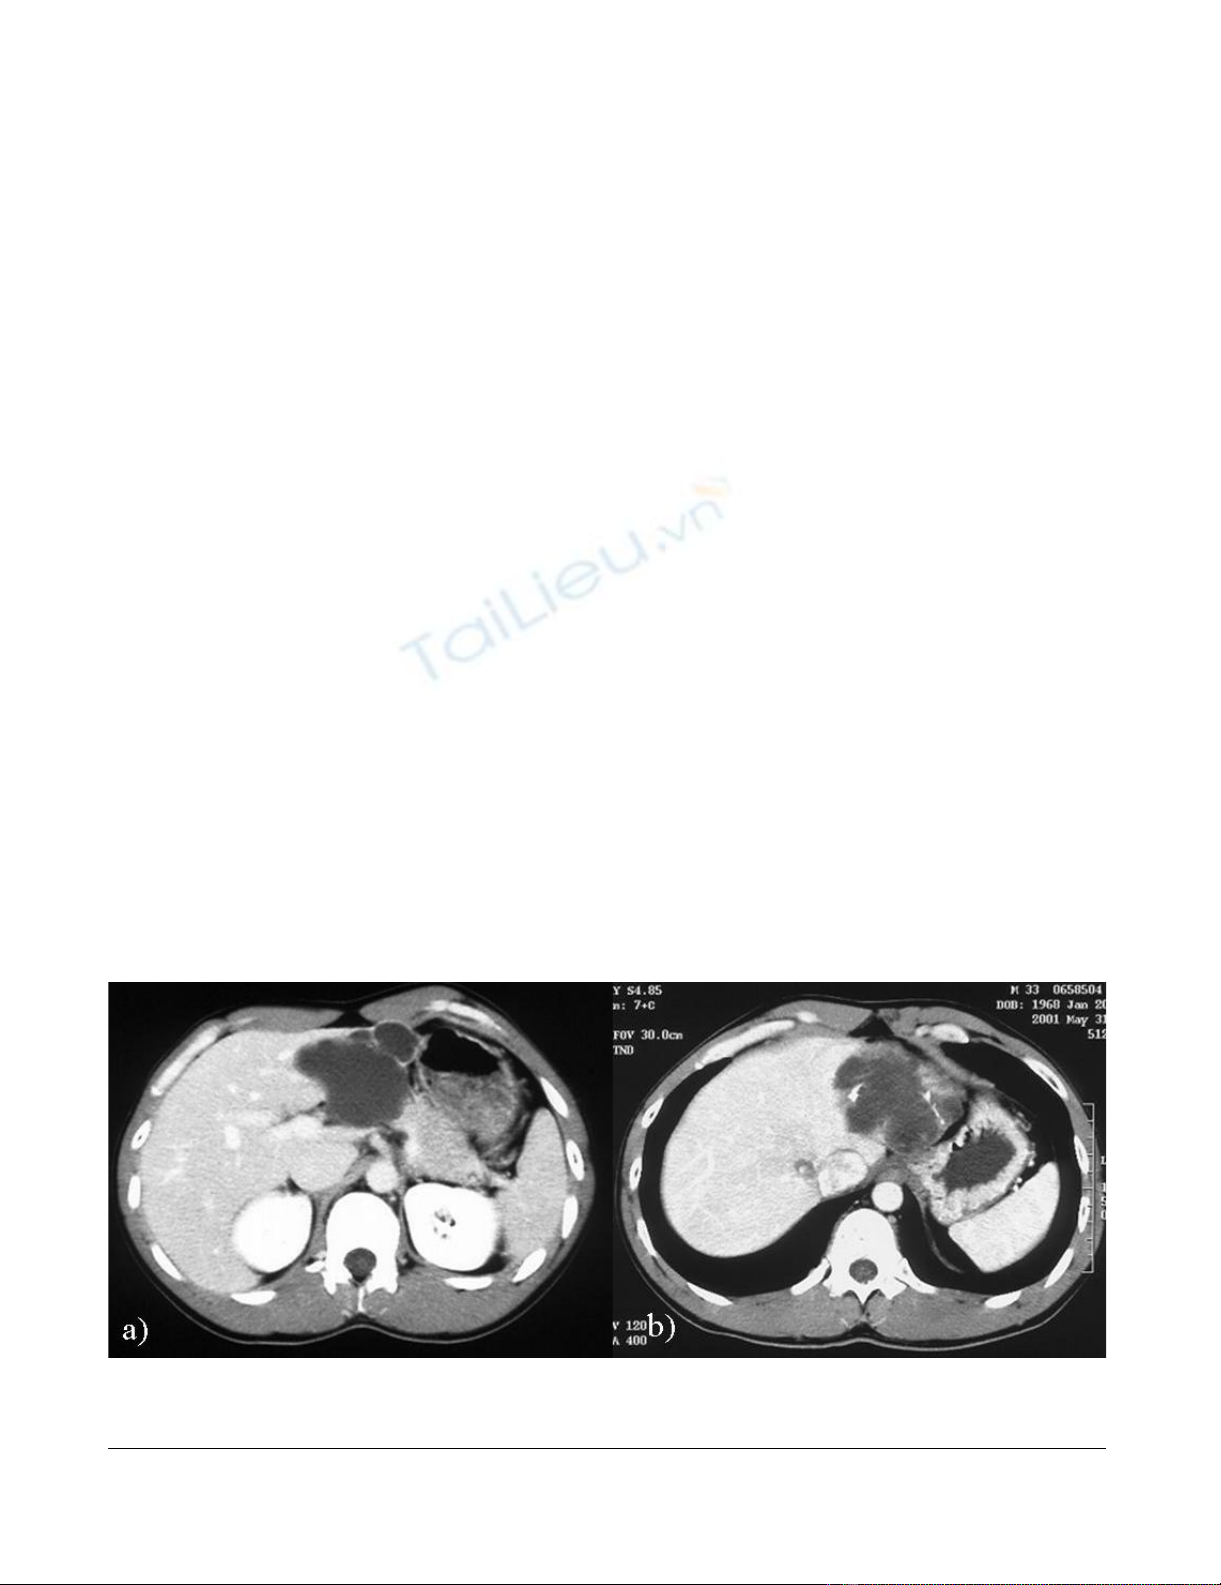

of simple hepatic cyst in 2004. In 1996 the cyst was

unilocular, 6 cm in diameter without calcification, septa

or papillary projections as observed by CT (Fig. 1a). In

2001 the cyst remained the same diameter but exhibited

calcification and septa (Fig. 1b). An abdominal CT per-

Abdominal CT findingsFigure 1

Abdominal CT findings. a) in 1996, showing the unilocular cyst 6 cm in diameter without calcification, septa and papillary

projections. No contrast enhancement was seen. b) in 2001, showing the same diameter with calcification and septa.